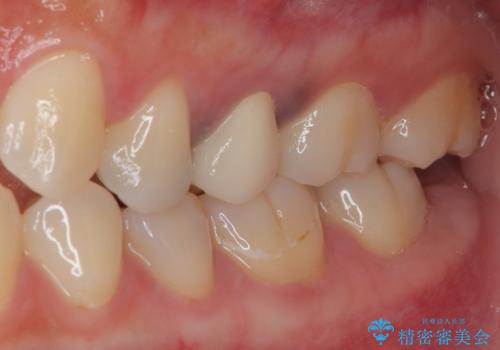

銀歯を気にせず思いっきり笑えるようになったと大変喜んでいただきました。

機能面においても問題なく、適合性の良い被せものをセットすることができました。